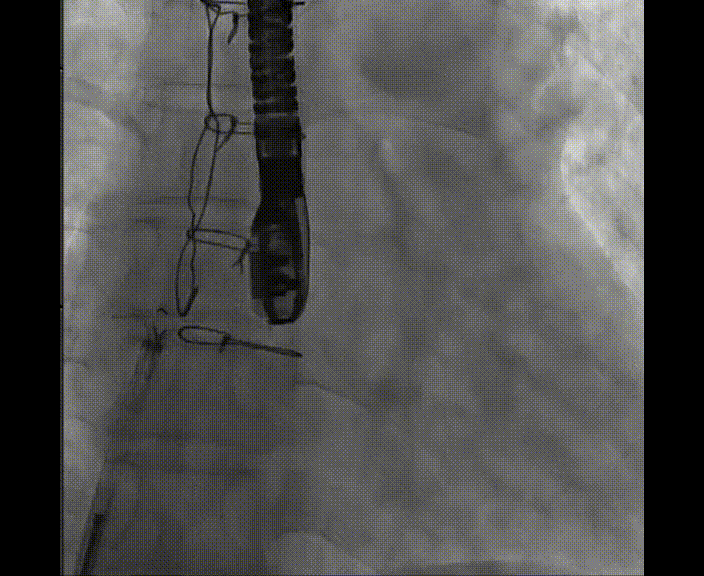

術(shù)中首先在局麻下穿刺股動(dòng)脈、股靜脈,完成心導(dǎo)管檢查評(píng)估后轉(zhuǎn)為全麻,在食道超聲引導(dǎo)下穿刺房間隔,穿刺成功后將加硬導(dǎo)絲送入左上肺靜脈建立軌道,根據(jù)患者病情行球囊預(yù)擴(kuò)張后植入6mm孔徑房間隔造孔支架,經(jīng)透視及食道超聲評(píng)估支架左右盤展開良好,夾持于房間隔兩側(cè),固定穩(wěn)定、位置良好,食道彩超顯示房水平右向左為主分流,分流孔直徑符合預(yù)期大小,心導(dǎo)管檢查評(píng)估達(dá)到預(yù)期效果,釋放造孔支架。術(shù)后12h患者下床活動(dòng),恢復(fù)順利,擬于近日完善術(shù)后評(píng)估后出院。